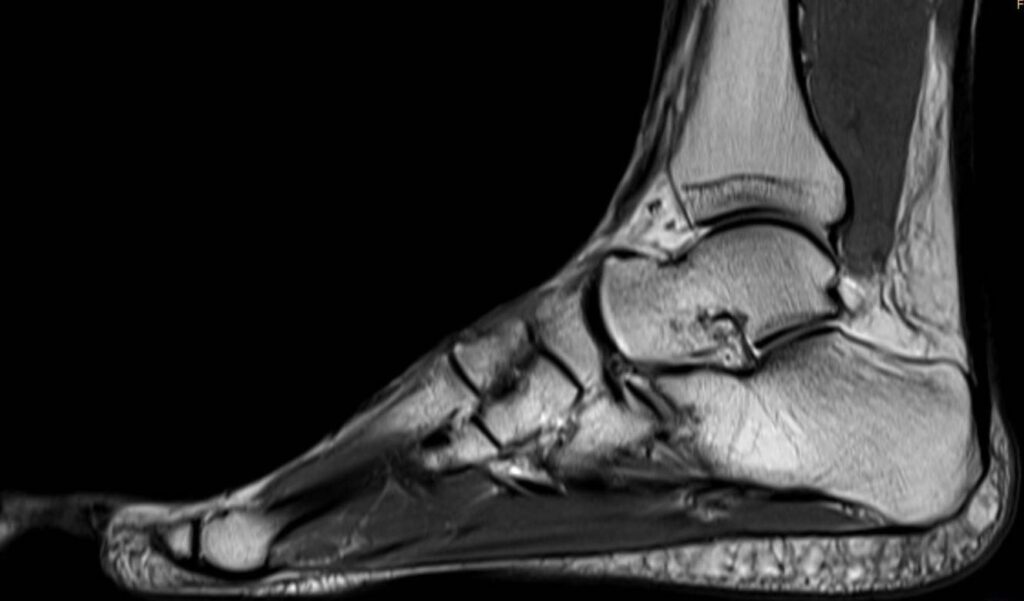

Eine Magnetresonanztomographie des Fußes, auch MRT Fuß genannt, ermöglicht die bildliche Darstellung der Strukturen im Fußinneren. Diese dient dazu, Veränderungen, Störungen oder Verletzungen im Fußbereich zu erkennen und zu beurteilen. Zusätzlich dient eine Fuß MRT dem Erkennen und Einschätzen von funktionellen Auswirkungen. Insbesondere eignet sich eine MRT Fuß zur Begleitung und Überwachung von Heilungsprozessen.

Eine MRT (Magnetresonanztomographie) des Fußes ist eine nicht-invasive diagnostische Bildgebungstechnik, die detaillierte Bilder der inneren Strukturen des Fußes liefert. Die MRT nutzt starke Magnetfelder und Radiowellen, um Schnittbilder der Gewebe im Fuß zu erzeugen, ohne dass ionisierende Strahlung (wie bei Röntgenstrahlen) verwendet wird. Die MRT Fuß ist hierbei ungefährlich und schmerzfrei.

Eine MRT des Fußes liefert detaillierte Bilder der verschiedenen Gewebetypen und Strukturen im Fuß, weswegen eine MRT am Fuß oftmals zum Ausschluss bzw. zur genauen Diagnostik von Verletzungen dient.

Fuß MRT Bild, verschiedene Perspektiven